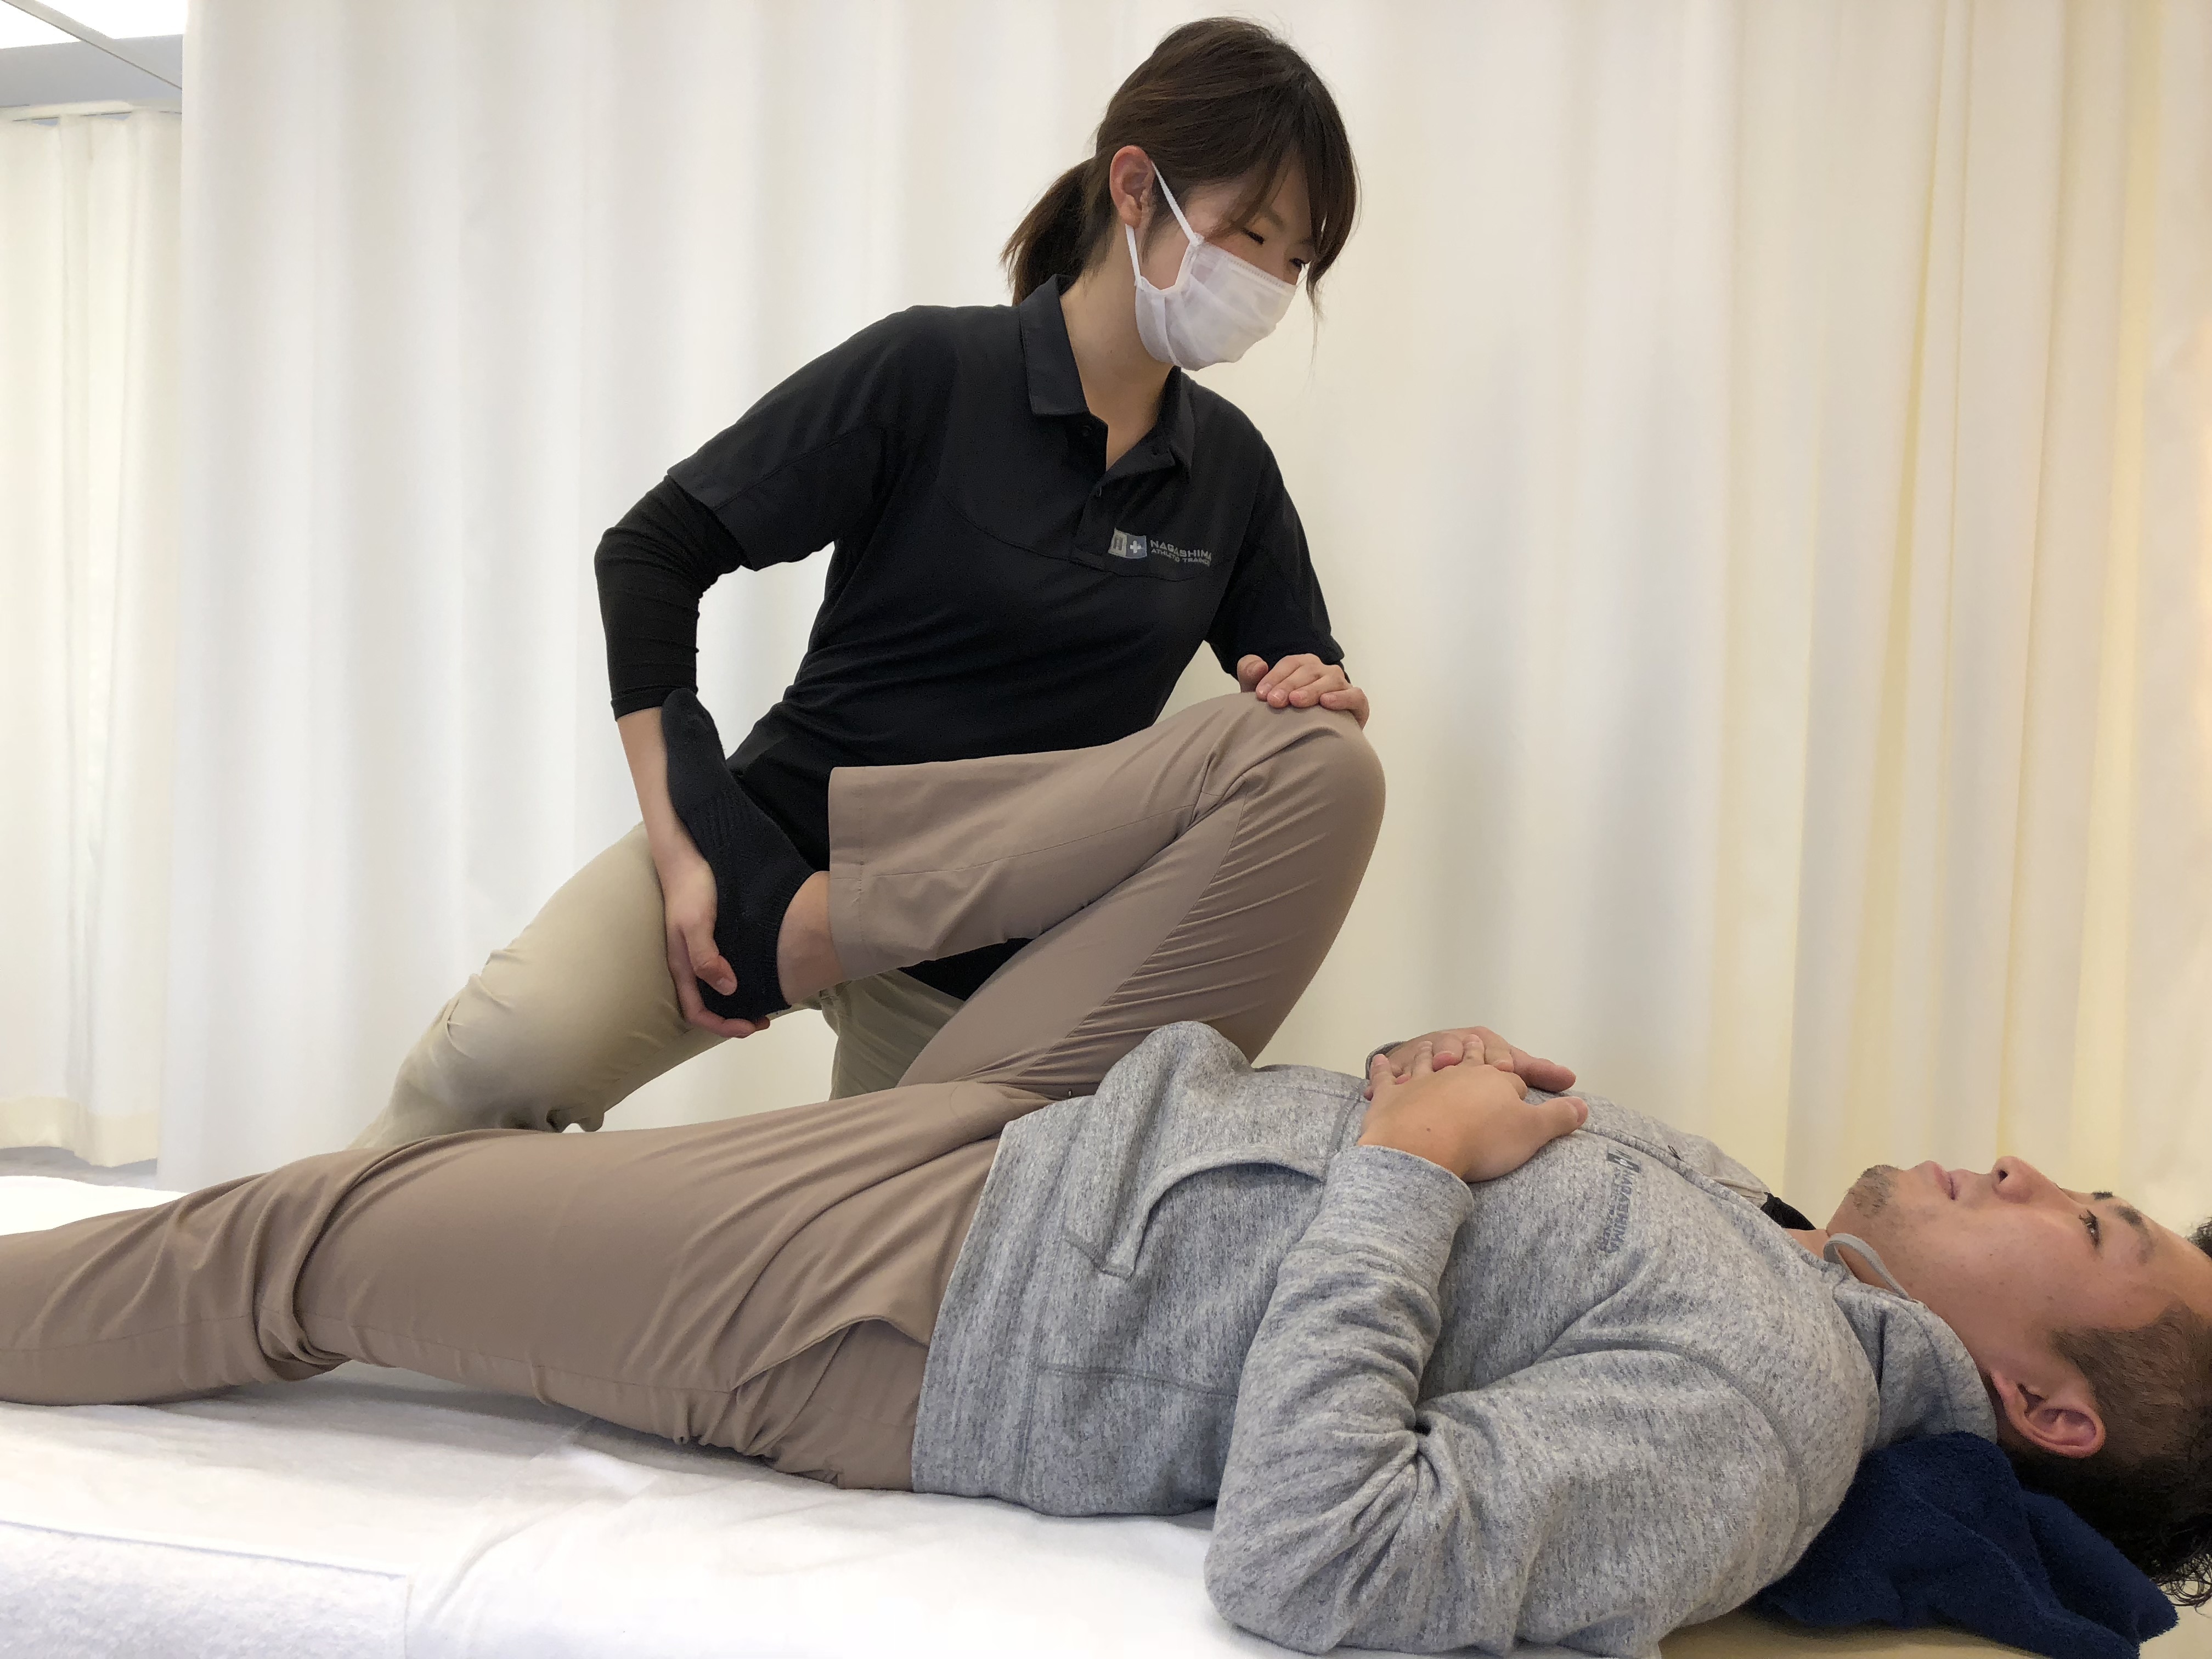

5. リハビリや運動に対するモチベーションを与える

リハビリ計画を遵守することが重要です。多くの人にとって、これは 1 日に 2 ~ 3 回 30 分間歩くことを意味します。医師は、1 日に 2 ~ 3 回、さらに 20 ~ 30 分間の運動を推奨することもあります。

歩いたり運動したりすると痛みを感じることがあります。これは正常です。患者がリハビリ計画を中止したいという意思を表明した場合は、彼らが感じていることはよくあること、リハビリが回復を早めるのに役立つことを思い出させてください。

自分の努力、結果、進捗状況をグラフ化できるようにすると、モチベーションを維持できる可能性があります。子どもたちと一緒に運動したり歩いたりすることも、子どもたちが順調に進むのに役立つかもしれません。